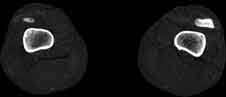

Visible Human male: Sectio transversalis 2271

CT

NMR

Pd                          / T2 \                         T1